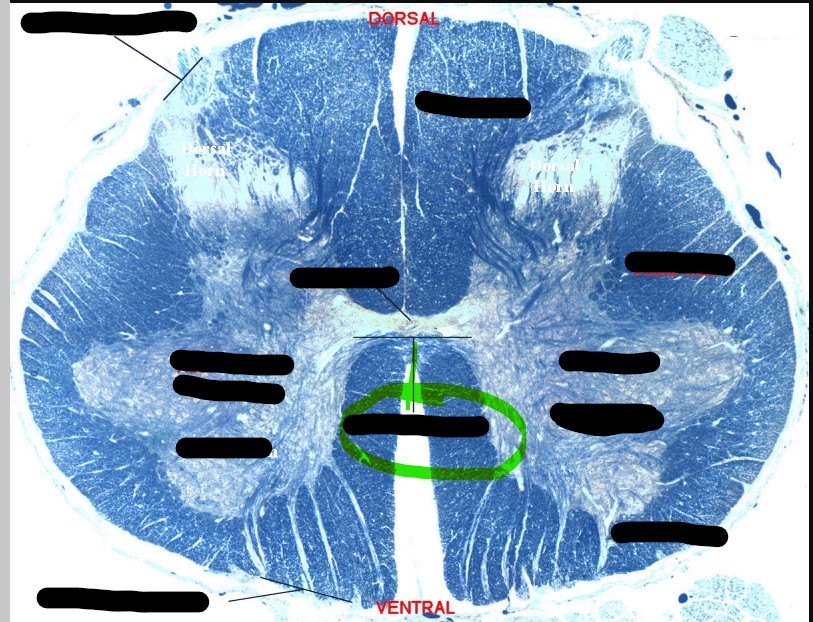

Spinal cord - gray matter

centrally located, and its shape resembles an H or a butterfly; subdivided into anterior horns, lateral horns, posterior horns, and gray commisure

Spinal cord - white matter

external to gray matter and partioned into three regions, posterior, anterior, and lateral funiculus

Spinal cord - dorsal column

contains ascending sensory pathways that carry information about tactile sensations and proprioception

Spinal cord - ventral column

anterio region where white matter is subdivided

Spinal cord - dorsal horn

left and right posterior masses of gray matter; axons of sensory neurons and the cell bodies of interneurons located here

Spinal cord - ventral horn

left and right anterior masses of gray matter; primarily house the cell bodies of somatic motor neurons which innervate skeletal muscle

Spinal cord - gray commissure

horizontal bar of gray matter that surrounds the central canal; primarily contains unmyelinated axons and serves as a communication route between the right and left sides of the gray matter

Spinal cord - lateral column

slight protrusion of gray matter of spinal cord into the lateral funiculus of either side; present only in the thoracic and upper lumbar

Spinal cord - central canal

hollow tube that runs the length of the spinal cord; filled with cerebral spinal fluid